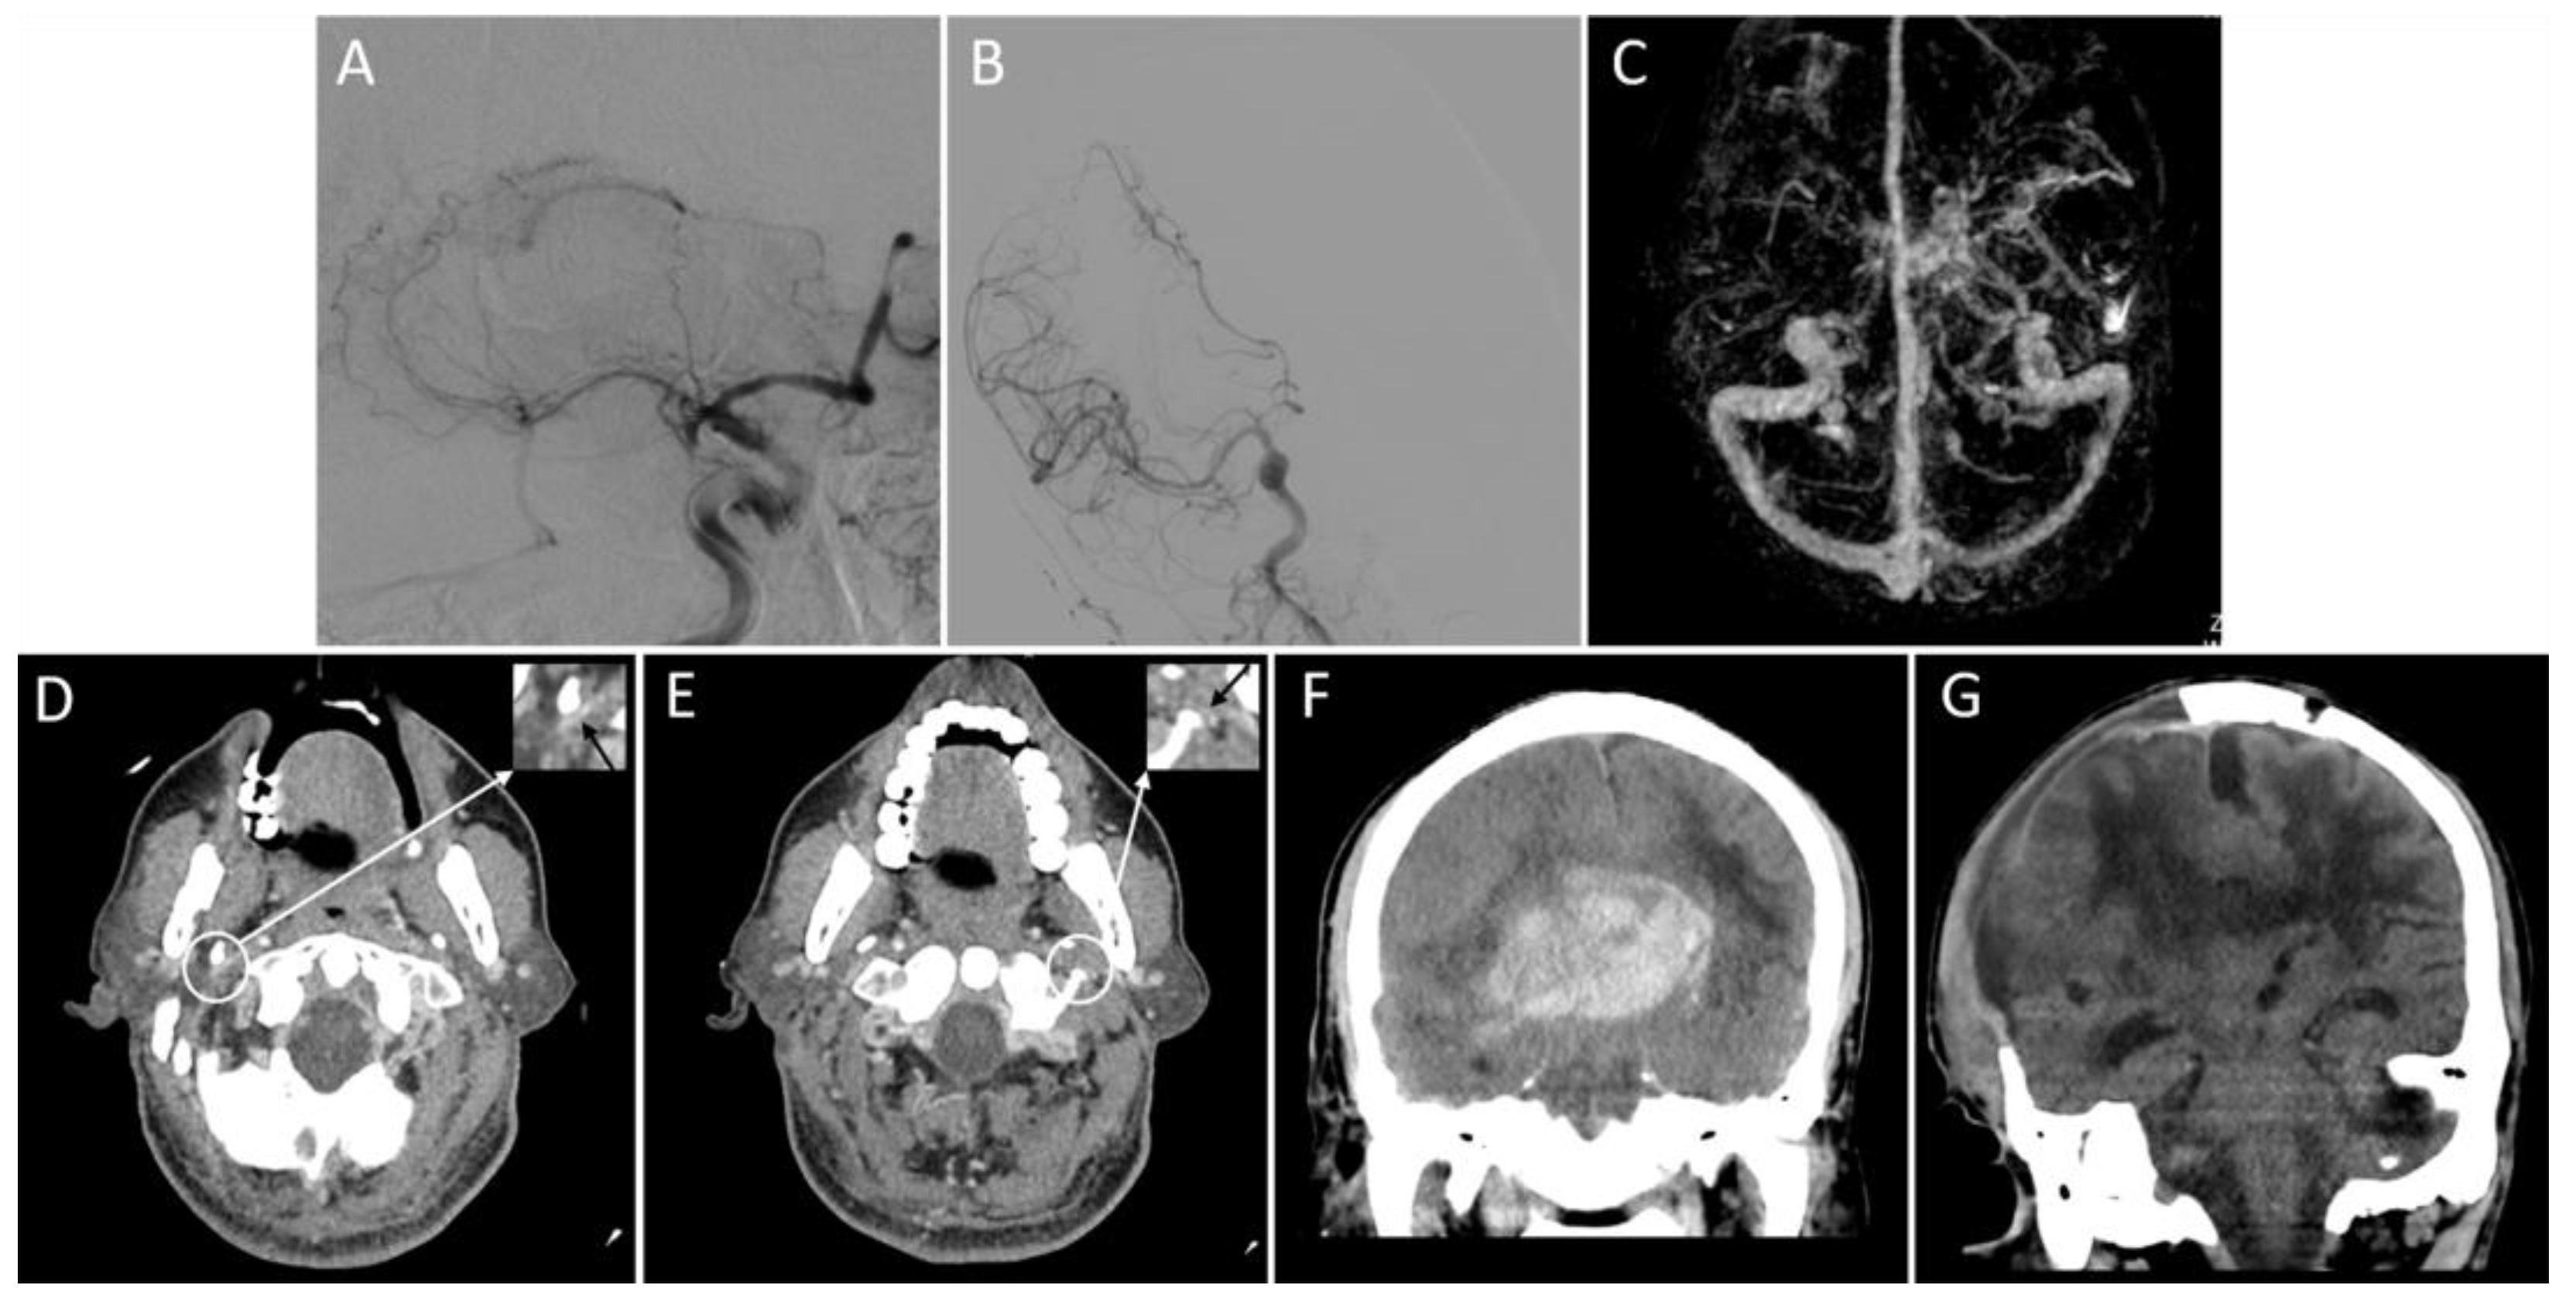

Figure 3.

Representative images of the outflow profile of internal jugular veins and outcomes. An adult patient with an acute right middle cerebral artery occlusion (A) was admitted with a National Institutes of Health Stroke Scale score of 19. The patient received a thrombectomy for 6 h following stroke onset and achieved successful reperfusion (modified thrombolysis in cerebral infarction score = 3) (B). Three-dimensional reconstructed computed tomography (CT) venography shows that the right transverse sinus is larger than the left (C), and bilateral internal jugular veins are severely narrowed on the axial CT angiography (D,E, black arrows). On the non-contrast CT scan within 24 h after thrombectomy, a parenchymal hematoma, midline shift, and subfalcine hernia are present (F). Sixteen days after thrombectomy (15 days after decompressive craniectomy), there is an apparent cerebral edema (G). The patient’s modified Rankin Scale score at discharge is 5.